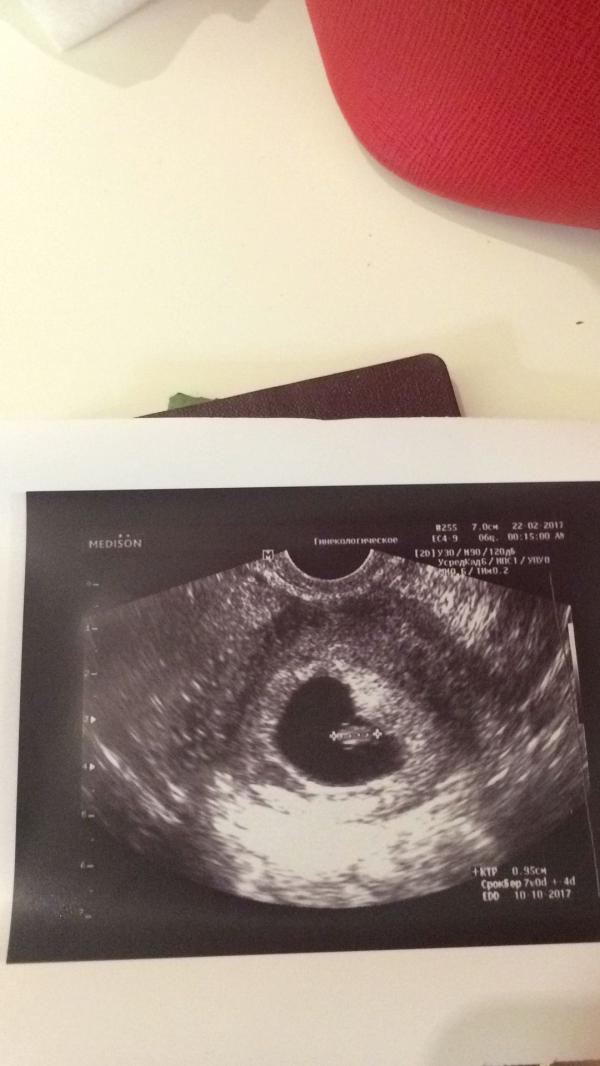

Ура! Скоро я снова стану мамой😊 решила отстреляться, так сказать))) пока к режиму "нережиму " привыкла,да и пока муж просит ещё одну принцессу)))живот,кстати, растёт быстрее😳 ах да, главное, опять в праздники не родить😅